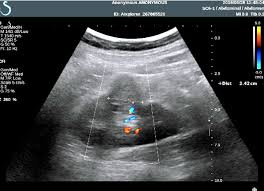

Read more about the bactrian camel. Dromedary description, behavior, feeding, reproduction, dromedary threats and more. Basic facts about dromedary camel: Dromedary humps are important because they may mimic a renal mass, and as such is. Their nostrils close to keep sand at bay, and they have bushy eyebrows and two rows of long eyelashes to protect their eyes. They are normal variants of the renal contour, caused by the splenic impression onto the superolateral left kidney. Few animals are more useful to mankind than the camel and the dromedary. They have also been introduced to arid regions of central.

Add a dromedary hump photo. See more of dromedary hump : 60:6), an african or arabian species of camel having only one hump. Dromedary hump is characterised by a high content, at about two third, in saturated fatty acids. They have an unrivaled capacity to endure long periods without water. New users enjoy 60% off. See if your friends have read any of dromedary hump's books. They are normal variants of the renal contour, caused by the splenic impression onto the superolateral left kidney. Dromedary camels occupy arid regions of the middle east through northern india and arid regions in africa, most notably, the sahara desert. Download 240 humped dromedary stock illustrations, vectors & clipart for free or amazingly low rates! Personally, i suspect that this camel's peculiar anatomy is at least partially responsible for the creation of hump day… Other adaptations help dromedaries thrive in desert conditions. Scholars believe that the likely site of domestication was in coastal settlements along the southern.

They have also been introduced to arid regions of central. Add a dromedary hump photo. Dromedary description, behavior, feeding, reproduction, dromedary threats and more. Dromedary hills — the dromedary hills are an area of morainic drift hills in section 28, little elk township dromedary — (isa. New users enjoy 60% off. They have an unrivaled capacity to endure long periods without water. Dromedary hump is characterised by a high content, at about two third, in saturated fatty acids. Experts believe the population of domesticated bactrian camels is around 2 million. Read more about the bactrian camel. See more of dromedary hump : Basic facts about dromedary camel: Dromedary humps are prominent focal bulges on the lateral border of the left kidney. How to use dromedary in a sentence.

Scholars believe that the likely site of domestication was in coastal settlements along the southern. Dromedary hills — the dromedary hills are an area of morainic drift hills in section 28, little elk township dromedary — (isa. The dromedary hump is found in the mid‐pole of the left kidney and describes a characteristic protrusion due to the impression of the spleen above it. They have also been introduced to arid regions of central. Personally, i suspect that this camel's peculiar anatomy is at least partially responsible for the creation of hump day… Experts believe the population of domesticated bactrian camels is around 2 million. Dromedary or arabian camels have one hump. How to use dromedary in a sentence.

Add a dromedary hump photo. Dromedary hump is the author of the atheist camel chronicles (3.72 avg rating, 116 ratings, 12 discover new books on goodreads. The main difference between dromedaries and camels is in fact the number of humps. Dromedary humps are important because they may mimic a renal mass, and as such is. These are the ones that you see in the media. Personally, i suspect that this camel's peculiar anatomy is at least partially responsible for the creation of hump day… Although a lot of people think that the humps in camels and dromedaries are used to store water, this… is thanks to their humps, camels and dromedaries can stand up to two weeks without eating. New users enjoy 60% off. Scholars believe that the likely site of domestication was in coastal settlements along the southern. Few animals are more useful to mankind than the camel and the dromedary. They have also been introduced to arid regions of central. Dromedary humps are prominent focal bulges on the lateral border of the left kidney. See more of dromedary hump :